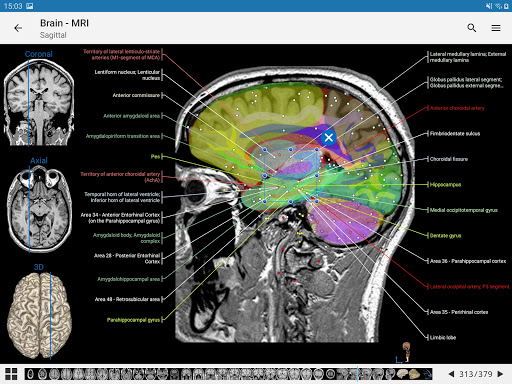

IMAIOS e-Anatomy adalah atlas anatomi manusia untuk dokter, ahli radiologi, mahasiswa kedokteran, dan teknisi radiologi. Dapatkan cuplikan lebih dari 26.000 gambar medis dan anatomi secara gratis sebelum berlangganan atlas anatomi manusia terperinci kami.

e-Anatomy memiliki lebih dari 26.000 gambar yang berisi serangkaian gambar dalam tampilan aksial, koronal, dan sagital serta radiografi, angiografi, gambar diseksi, bagan anatomi, dan ilustrasi. Semua gambar medis diberi label dengan cermat, lebih dari 967.000 label tersedia dalam 12 bahasa termasuk Terminologia Anatomica Latin.

- Gulir set gambar dengan menyeret jari Anda

- Perbesar dan perkecil

- Ketuk label untuk menampilkan struktur anatomi

- Pilih label anatomi berdasarkan kategori

- Mudah menemukan struktur anatomi berkat pencarian indeks